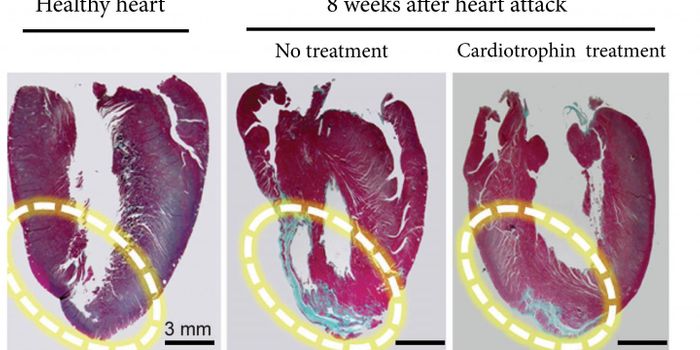

SEP 22, 2017CardiologyWhy can’t humans regrow their organs like some organisms can? It certainly would help repair some of the damage do ...

NOV 23, 2016CardiologyMany organisms are capable of regenerating limbs. Why not humans? New research could help humans experience the benefits ...